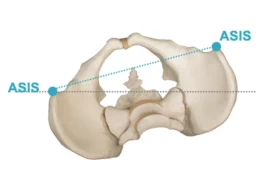

عدد الانحناءات يعني عدد المناطق التي يخرج فيها العمود الفقري عن شكله المستقيم الطبيعي عند النظر إليه من الخلف.

يكون العمود الفقري منحنيًا في اتجاه واحد فقط، وغالبًا يكون شكله أقرب إلى حرف C.

يظهر العمود الفقري بشكل أقرب إلى حرف S، حيث يعوض الجسم انحناءً بانحناء آخر للحفاظ على التوازن.

الأشعة السينية هي الأساس في تحديد:

موقع كل انحناء (صدري، قطني، أو مختلط)

اتجاه الانحناء

درجة كل انحناء على حدة

من خلال الأشعة يمكن رؤية العمود الفقري بالكامل وتحديد كل انحناء بوضوح.